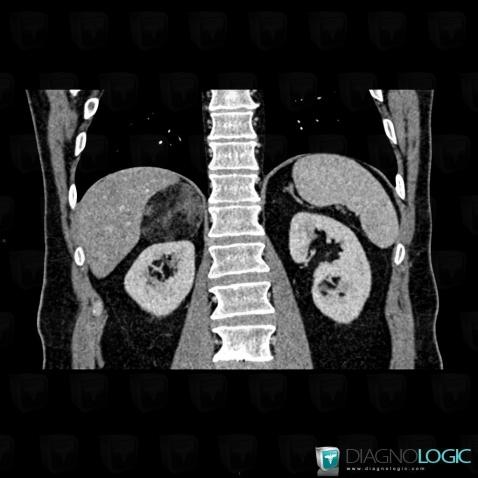

Myélolipome, Surrénales, Scanner

Voici les informations spécifiques à l'image clé ci dessus:

- Diagnostic Myélolipome, Localisation(s) Surrénales, comportant les gammes Masse surrénalienne unilatérale